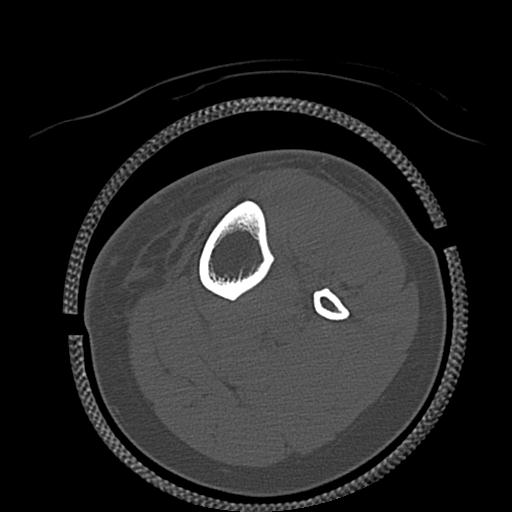

102803 1/12(キウスなし) 1/27 左下腿 4R 30歳女性 左脛骨軸内釘